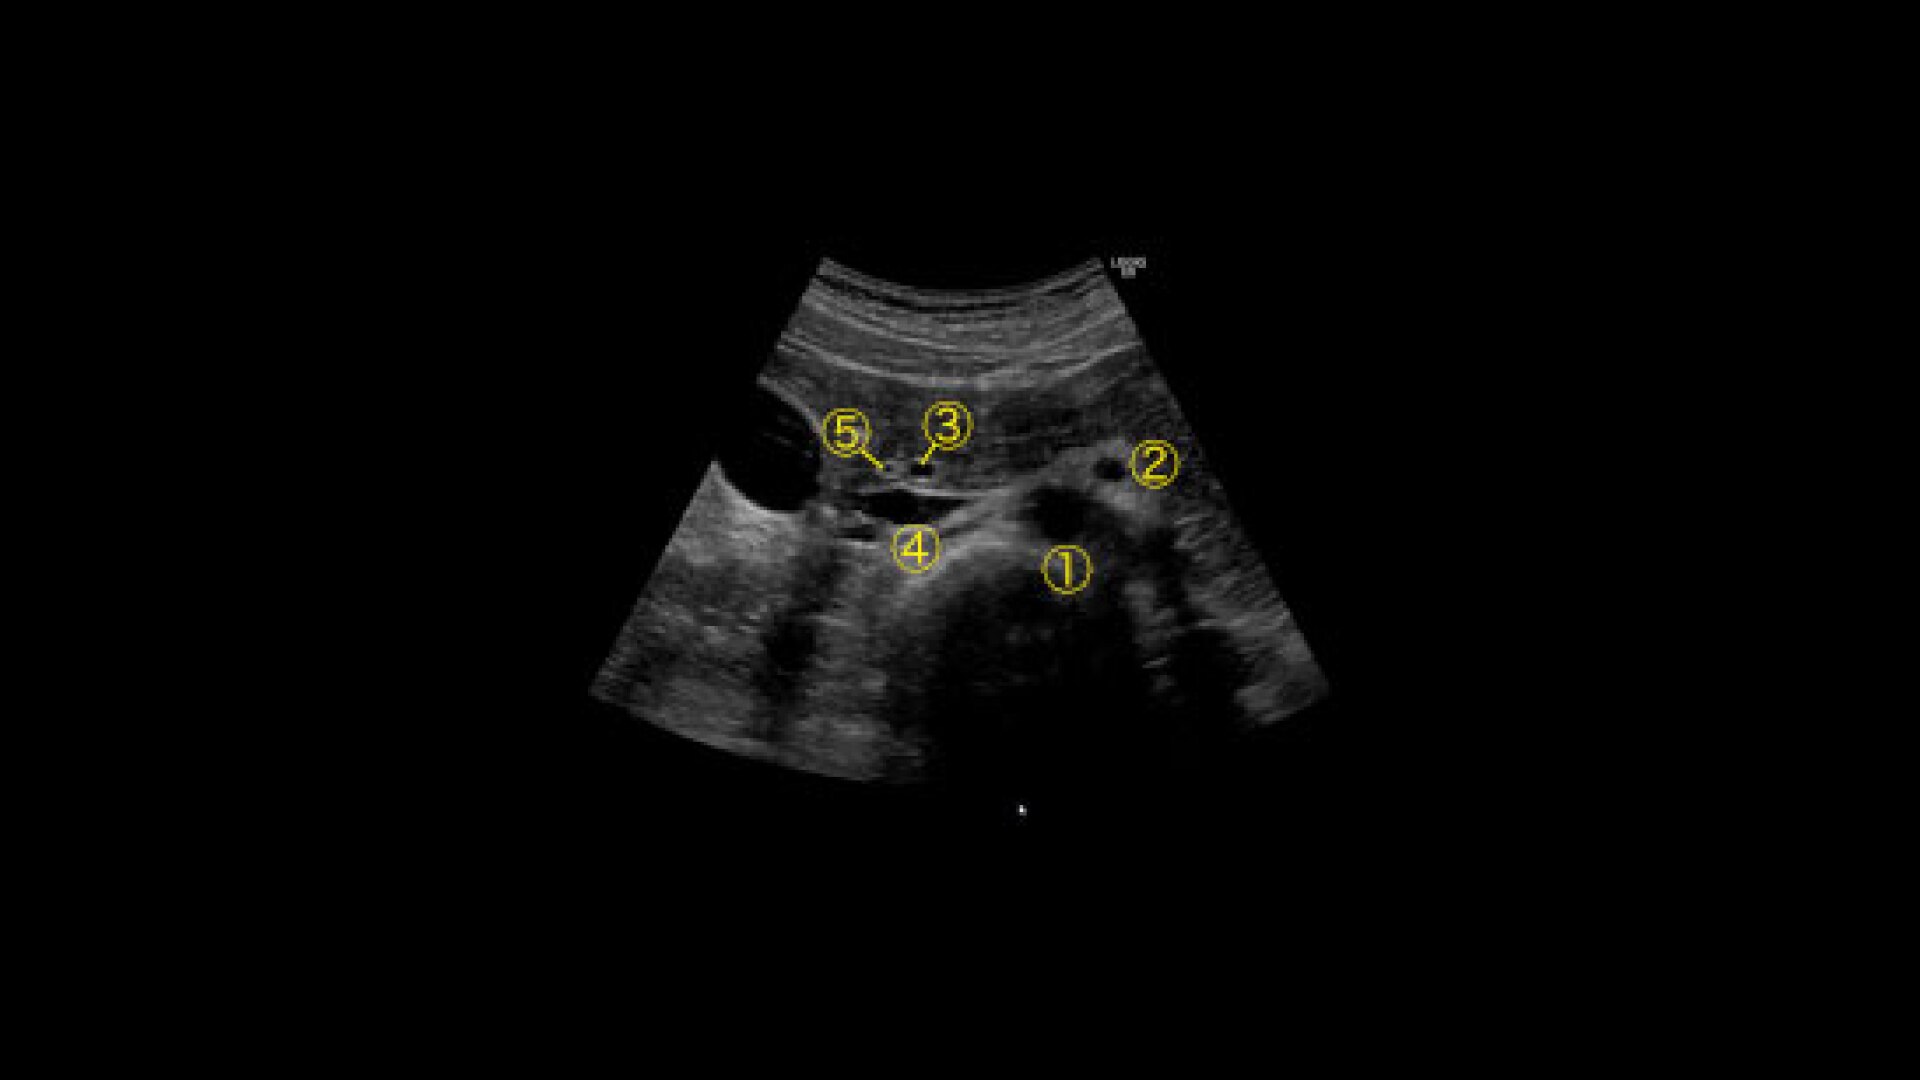

POLYVALENCE

Très flexible ces antennes s’adaptent à toutes les morphologies.

CONFORT

Une couverture enveloppante